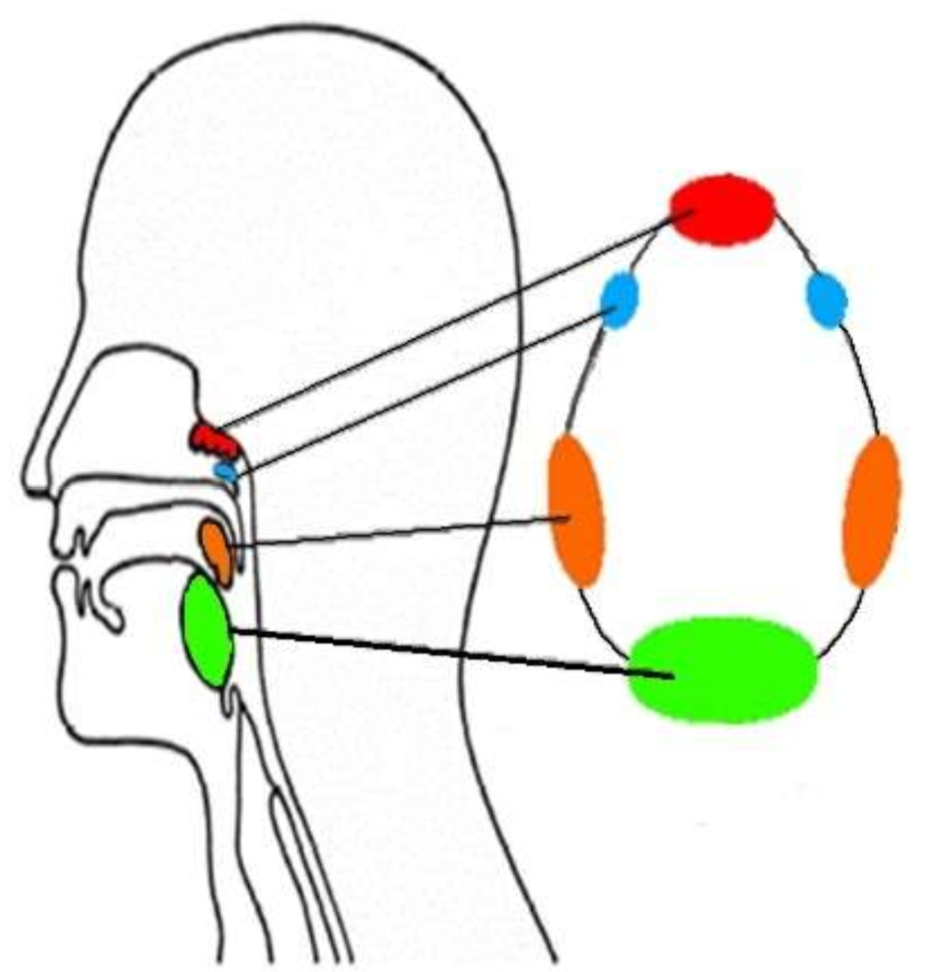

What is this group of structures called?

waldeyers ring

What is in red?

pharyngeal tonsil

What is in blue?

tubal tonsils

What is in orange?

palatine tonsils

What is in green?

lingual tonsil